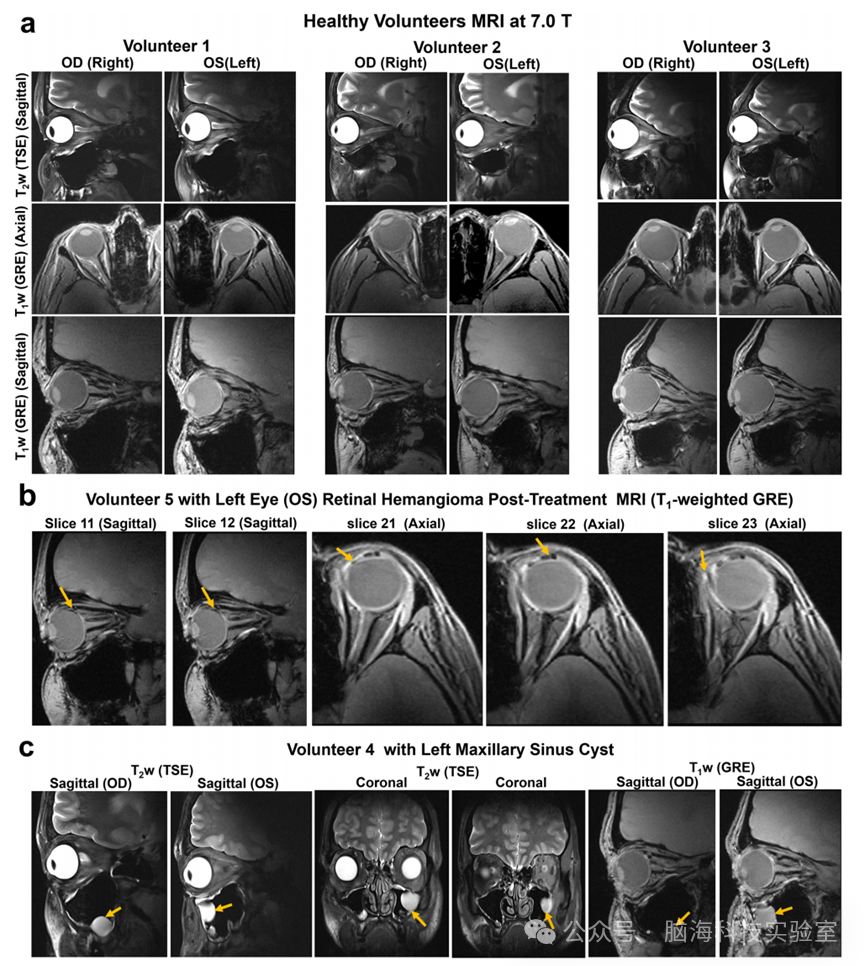

在健康志愿者的活体成像中,Bend-MTMA展示了显著的性能优势。三名志愿者接受B1+ mappingT2加权TSET1加权GRE成像。Bend-MTMA相比Bend-Loop,眼内B1+提升10-40%T2信号增强25-51%T1信号增强7-26%,且双侧对称性明显改善。重复性实验显示该天线性能稳定。

在临床可行性研究中,一名视网膜血管瘤患者(Von Hippel-Lindau病)术后16天接受Bend-MTMA扫描,清晰显示了病灶区域的瘢痕组织和未治疗的血管畸形。另在一名健康志愿者中意外发现左上颌窦囊肿。

12 高分辨率眼部解剖成像及临床病例:视网膜血管瘤术后改变及鼻窦囊肿